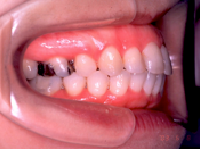

1) 主訴 上の歯が出ており、口が閉じにくい 発音が悪い

2) 診断名 上顎前突

3) 初診時年齢 15歳

4) 治療に用いた装置 ストレートタイブマルチブラケットシステム(018x025スロット)

パラタルバー、前歯はセラミックブラケット

5) 抜歯 左右上顎第一小臼歯、下顎左右下顎第二小臼歯(計4本)